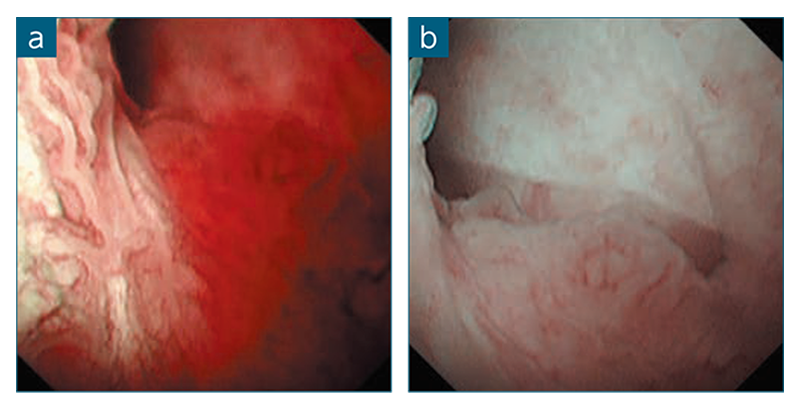

症例提示:内視鏡的乳頭切除術(EP)後に胆管・膵管へのステント留置を行った症例

当院では、EPの際は水中で腫瘍をスネアリングし、乳頭が腸内腔へ伸長しないよう工夫している。また、CO₂送気は腫瘍切除後ではなくクリッピング終了後に行うことで、開口部の創傷を防止している。EP施行後は画像出力をWLIからTXIに切り替え、開口部の凹み構造 や膵液の流出点を目印に総胆管・膵管開口部の位置を把握することが可能であった(図1)。同定した総胆管・膵管開口部に対し、膵管、総胆管の順にカニューレ挿入とプラスチックステント留置を行い、ゲル状の吸収性局所止血材を創部に適用して手技を終了した。

図1 TXIモードにより内視鏡的乳頭切除術(EP)後の総胆管・膵管開口部を同定 : WLI(a)、TXIモード1(b)